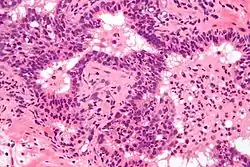

Биопсия предстательной железы при остром простатите не показана, так как может способствовать распространению инфекции или дополнительному инфицированию простаты ещё одним типом микроорганизмов. Кроме того, биопсия предстательной железы как диагностическая процедура при остром простатите просто не требуется, поскольку характерные клинические признаки и симптомы, а также данные пальцевого исследования предстательной железы, анализов крови, мочи и мазков из мочеиспускательного канала обычно позволяют поставить правильный диагноз и без биопсии. Гистологическим коррелятом острого простатита является нейтрофильная инфильтрация ткани предстательной железы.